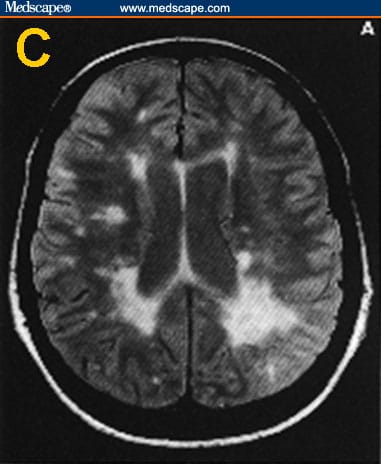

35+ Lyme Disease Brain Scan UK. The neurological symptoms of lyme disease are some of the most confused with other illnesses. Lyme disease is a bacterial infection transmitted to humans through tick bites.

Lyme disease, also known as lyme borreliosis, is an infectious disease caused by the borrelia bacterium which is spread by ticks. Research into the connection between lyme disease and the brain has found that lyme causes swelling in the brain. Intravenous antibiotics are recommended if a person has meningitis, inflammation of the lining of the brain and spinal cord, or more severe heart problems.